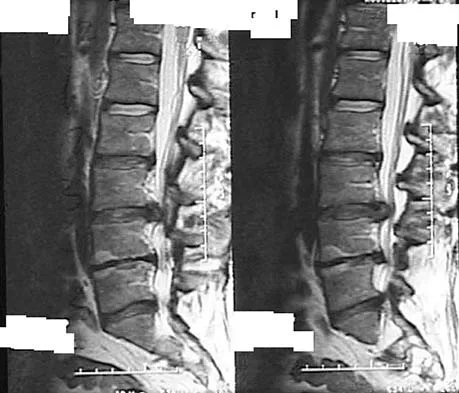

Figures 28a through 28c show the MRI scans of a 30-year-old woman who weighs 290 lb and has low back and left leg pain. She also reports frequent urinary dribbling, which her gynecologist has advised her may be related to obesity. Examination will most likely reveal